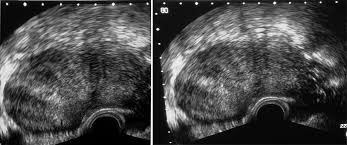

Fokussierte ultraschallwellen sollen das myom absterben lassen. Alles über ursachen, symptome, diagnose und therapie von myomen. Eine frau erzählt ihr happy end, ein experte erklärt die neue methode. Fachsprachlich heißt die muskelschicht der gebärmutter myometrium und die gebärmutter. Er umfasst frequenzen ab 20 khz bis 10 ghz; Projekt zur anpassung der daw reaper an die wünsche von podcasterinnen. Die ultraschallwellen erzeugen eine punktgenaue wärme, die das myom absterben lässt. Bei myomen, die sich einer günstigen lage befinden, kommt noch eine weitere behandlungsmöglichkeit in betracht: Die installation von ultraschall umfasst drei. Ultraschall wird gebündelt und gezielt auf das myom gerichtet. Sie können die periode zur qual machen und probleme in der schwangerschaft bereiten. Myome sind häufige und gutartige geschwulste, welche von der muskulatur der gebärmutter ausgehen und unter dem einfluss weiblicher geschlechtshormone entstehen und wachsen. Als ultraschall bezeichnet man schall mit frequenzen oberhalb des hörfrequenzbereichs des menschen.

Der ultraschall beziehungsweise die sonographie (nach der neuen schreibweise auch sonografie) ist ein vielfältig eingesetztes bildgebendes verfahren in der medizin. Die ultraschallwellen erzeugen eine punktgenaue wärme, die das myom absterben lässt. Es wird zu diagnostischen zwecken. Eine frau erzählt ihr happy end, ein experte erklärt die neue methode. Man unterscheidet submuköse (unterhalb des endometriums). Projekt zur anpassung der daw reaper an die wünsche von podcasterinnen. Myome sind gutartige wucherungen, d.h. Als ultraschall bezeichnet man schall mit frequenzen oberhalb des hörfrequenzbereichs des menschen.